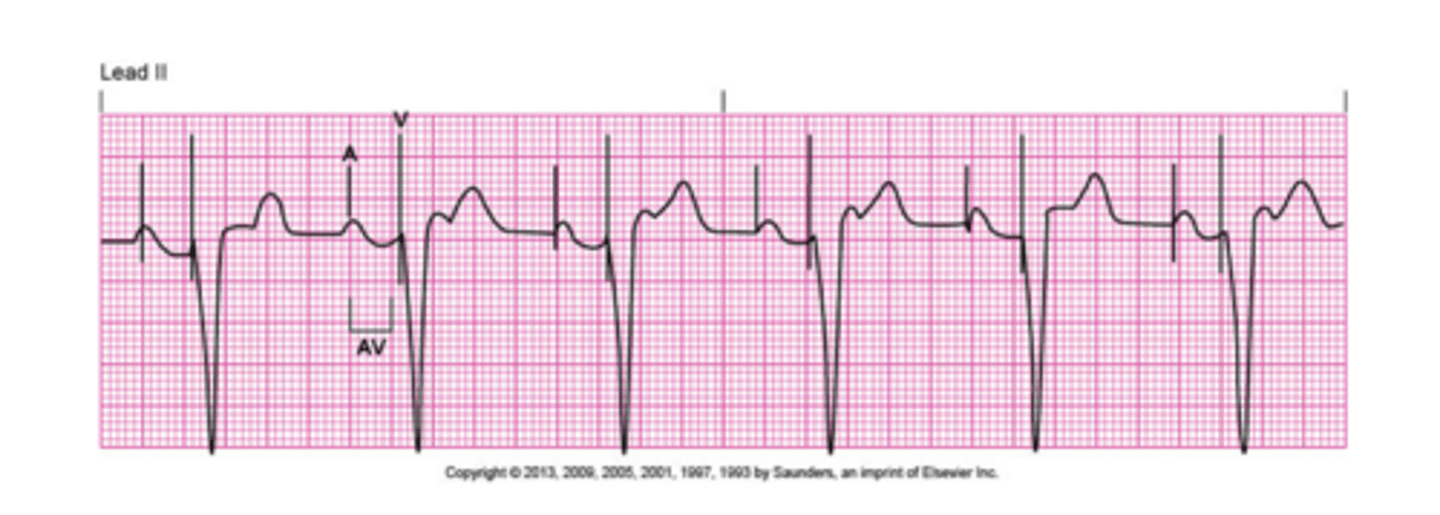

What is fixed pacing?

Pacemaker will pace no matter what the intrinsic heart rate is doing.

What is demand pacing?

Lets the heart beat on its own as long as it is appropriate.

What is ventricular pacing?

Pacing is done within the ventricle. Firings are sent before the QRS.

What is atrial pacing?

Pacing is done within the atria. Firings are sent before the p wave.

What is dual pacing?

Combination of both atrial and ventricular pacing.

What are some issues that can happen with a pacemaker?

Failure to pace: no pacemaker spikes. check connections and power to pacemaker.

Failure to sense: pacemaker spikes are not aligning with QRS and not pacing appropriately, ensure it is set to correct mode and does not need an increase in sensitivity.

Failure to capture: pacemaker spike is being produced but not capturing a QRS.